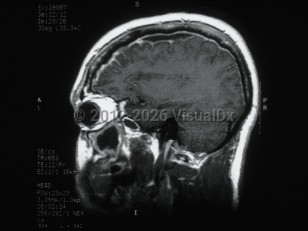

Subdural empyema is a collection of pus in the space between the dura and the arachnoid. Infection of the paranasal sinuses is a risk factor for cranial subdural empyema, as the infection can spread to the space by way of emissary veins. Contiguous spread of infection from osteomyelitis of the skull, meningitis, mastoiditis, or otitis media are also possible. Other etiologies include trauma, seeding of an existing subdural hematoma, or postoperative infection. These infections are typically polymicrobial.

Hematogenous seeding of the space is more likely to result in spinal subdural empyema. This location is less common, accounting for less than 5% of subdural empyema. Staphylococcus aureus is often implicated in infections in this location. Patients may present with fever, headache, and altered mental status (or some combination of these symptoms). Focal neurological signs and seizures may also be present. Magnetic resonance imaging (MRI) with contrast is the diagnostic test of choice.

Treatment is with a combination of surgical decompression and antibiotic therapy. Complications include cerebritis, cerebral abscess formation, and venous sinus thrombosis. Morbidity and mortality in subdural empyema is directly related to delay in therapy.